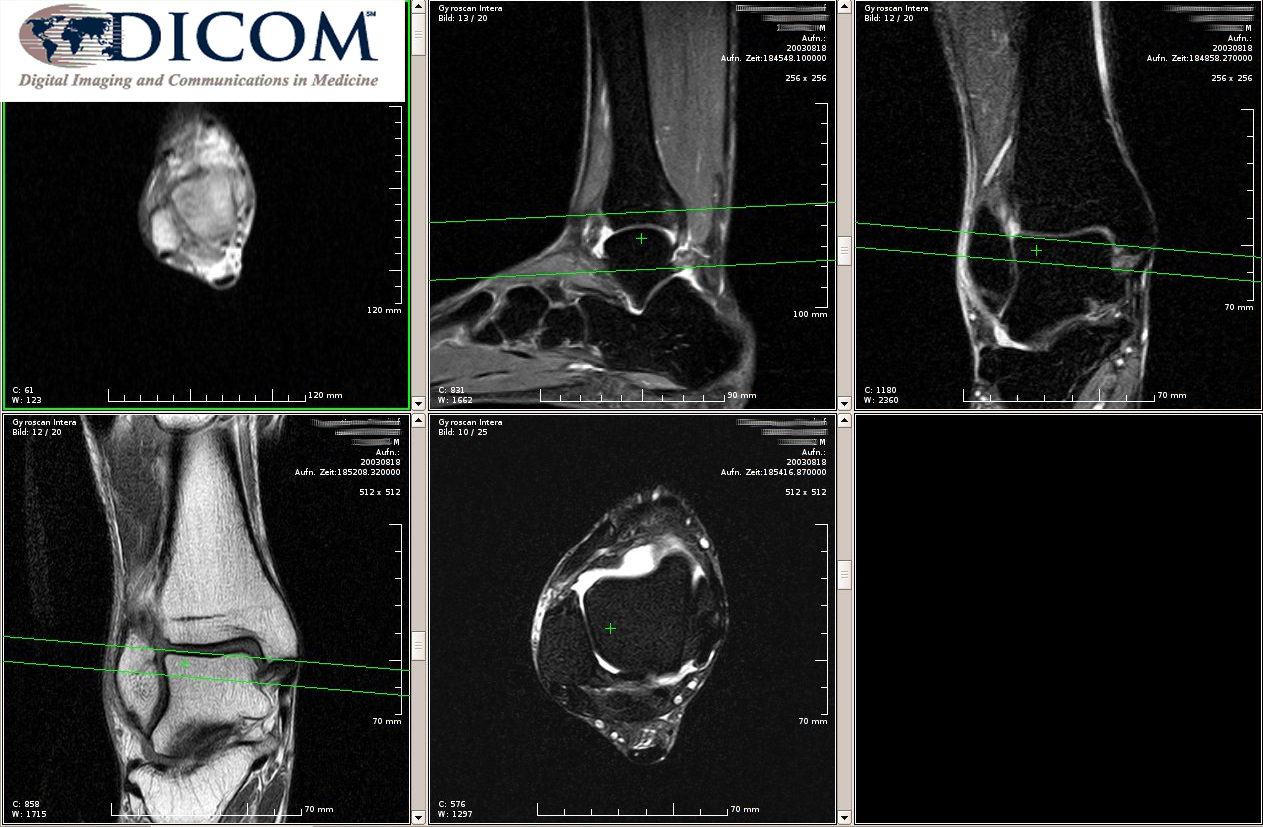

• Получать от медицинской аппаратуры информацию о выполненных исследованиях в виде текстовой информации или изображений и передавать ее в медицинскую карту пациента;

Модуль DICOM поддерживает работу с медицинским оборудованием, выдающим результаты исследований в виде текста или графической информации. Поддерживается такая аппаратура, как:

• МРТ-сканеры;